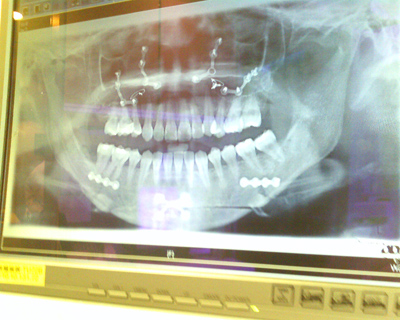

↑ 術後X 光片﹐看到上下顎密密麻麻的鋼釘了嗎? 我現在經過機場閘門都會嗶嗶叫喔~ (得意貌)

話說正顎手術的方式主要有2 種

一種正如我所做的﹑是以鋼釘為輔助幫助顎骨愈合

恢復期間只有前3週的時間很難開口+說話+進食﹑6週後便能上矯正器

但相對的鋼釘也會一輩子留在骨頭上